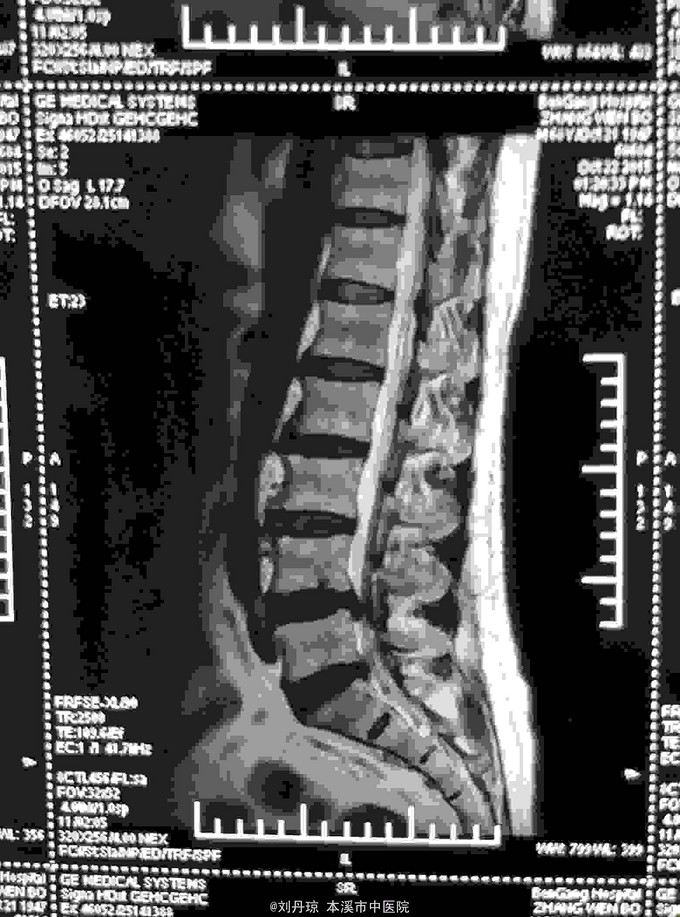

腰部间歇性钝痛伴左下肢放射痛麻木感半年。患者半年前无明显诱因感腰部间歇性钝痛伴左下肢放射痛麻木感,经多家医院治疗未见明显好转,今日来我院门诊求治,门诊医师以“ 腰椎间盘突出症、骶管囊肿 ”收入院治疗。

L4-S1棘突左侧1厘米压痛阳性,直腿抬高试验左40º右60º,加强试验左侧(阳性)右侧(阴性),腰椎功能障碍。左腿前外侧及足背外侧感觉减弱。 辅查CT: 腰椎间盘突出症、骶管囊肿

腰椎间盘突出症、骶管囊肿 治疗:骶管注射、甘露醇注射液静点、神经营养药物静点、小针刀治疗、中药熏药治疗、雷火灸治疗